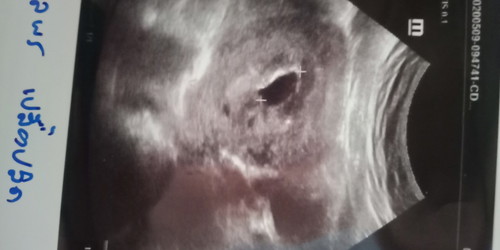

กลมๆดำในภาพคือ ถุงการตั้งครรภ์ค่ะ อายุครรภ์คงน้อยมากๆ ไม่รู้ว่าประจำเดือนวันแรกของครั้งสุดท้ายที่มาของคุณแม่วันที่เท่าไร แต่เจอแบบนี้หมอคงนัดซาวด์ซ้ำอีกรอบค่ะ

เห็นแต่ถุงตั้งครรภ์ แต่ยังไม่เห็นตัวอ่อน

ถุงตั้งครรภ์ค่ะ ตอนนั้น 7w ปัจจุบัน 13w แล้วค่ะ

เห็นเเต่ถุงตั้งครรภ์จ้า ยังไม่เจอตัวอ่อน

เครื่องบอกประมาน6สัปดาคะ